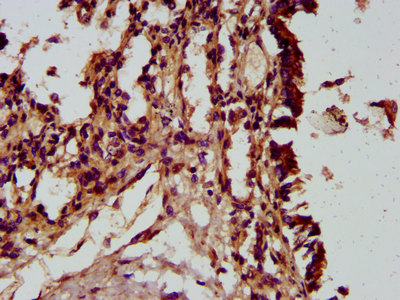

![]() | IHC image of PACO58188 diluted at 1:300 and staining in paraffin-embedded human lung tissue performed on a Leica BondTM system. After dewaxing and hydration, antigen retrieval was mediated by high pressure in a citrate buffer (pH 6.0). Section was blocked with 10% normal goat serum 30min at RT. Then primary antibody (1% BSA) was incubated at 4°C overnight. The primary is detected by a biotinylated secondary antibody and visualized using an HRP conjugated SP system. |